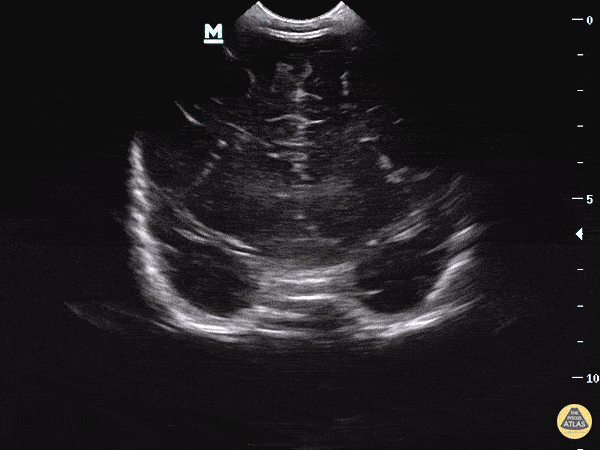

Pediatrics - Head Imaging - Coronal Plane

Please see our blog post for further information on this topic. The coronal plane has the indicator marker to the right and is placed on the anterior fontanelle. The ultrasound beam is swept from the anterior to posterior aspect of the head. Dr. Sathya Subramaniam - Childrens Hospital of Philadelphia Pediatric, EM Ultrasound